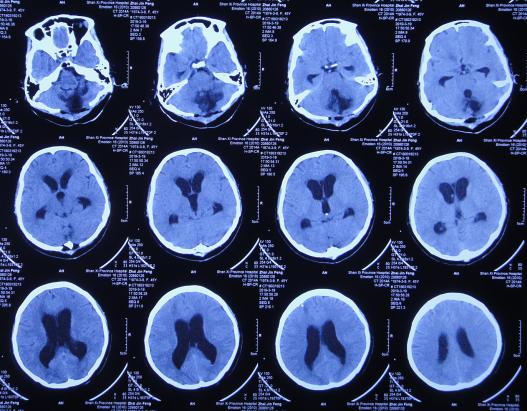

脑出血脑室外引流术12天即2019年3月2日,查头颅CT示出血完全消失,但脑室稍有扩大( 图-6 )。

图-6: 2019年3月2日头颅CT

脑出血脑室外引流术后2周,为防止发生颅内感染拔除了脑室外引流管。脑出血脑室外引流术后20天,意识再次变差浅昏迷,为进一步治疗于脑出血后21天即2019年3月11日(拔除脑室外引流后1周)转至第2家的上级的山西省某省级的三甲医院;入院后查头颅核磁示脑积水( 图-7 )。

住院10天左右的时间内给予腰穿3次,脑脊液培养均无菌生长,期间2019年3月19日查头颅CT示仍脑积水( 图-10 )。

图-10: 2019年3月19日头颅CT

在第3家医院住院大约64天时间内,期间(2019年3月29日、2019年4月28日)查头颅CT虽均示脑室扩张( 图-11、图-12) 。

图-11: 2019年3月29日头颅CT

图-12: 2019年4月28日头颅CT